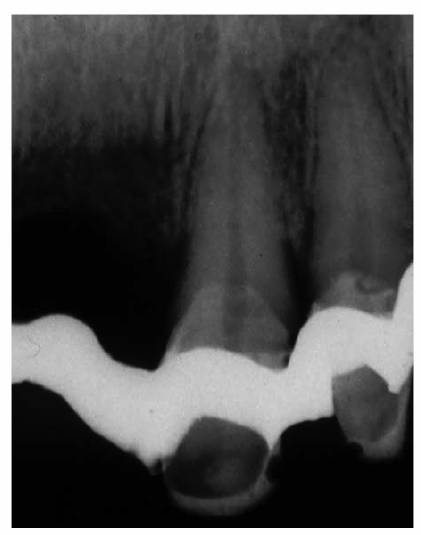

Precementation Radiographs

Prior to cementation, Yamada (personal communication, 2001) re-radiographs the

prepared teeth (Figures 19-25A

and B).

These images check the pulpal, periapical, and periodontal status of the teeth.

Also, the radiographs, unencumbered by the presence of the metal castings,

provide a chamber/canal road map record if the tooth requires endodontics in

the future. This may appear pessimistic, but Arens and Chivian reported that

over 40% of teeth requiring root canal therapy are crowned.4 Prior

knowledge of the size, location, and direction of the chamber and the canal will

reduce the possibility of (1) crown damage during access opening, (2) lost time

searching for the canal orifice, (3) perforations of the chamber or the canal

because of disorientation, (4) natural core elimination by gutting, (5) crown

dislodgment, and (6) sufficient destruction to alter the situation and require

corrective surgery. Each of these iatrogenic possibilities reduces the

prognosis and jeopardizes the tooth's reliability as an abutment.

Figure 19-25A and B: Precementation radiographs provide a road map to the canals if endodontic therapy is necessary after cementation of the castings. (Radiographs courtesy of Dr. Henry Yamada.)